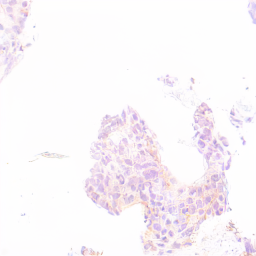

HER2 Dataset. The first histopathological dataset used in this work consists of tissue sections from breast cancer, immunohistochemically stained for Human Epidermal growth factor Receptor 2 (HER2) expression [14], with 600 Whole Slide Images from as many patients, digitized using a 20x objective on a PANNORAMIC 1000 scanner from 3DHistech. For 40 patients, manual segmentation annotations are available for twelve Region of Interest (ROI) each. A medical student created manual segmentation annotations of tumor tissue for 32 patients for training and validation, while a pathologist annotated the remaining eight for testing. The 560 patients without annotations serve as a style source during image generation. To test the method with varying amounts of data, we use 24, 12, or 4 annotated patients.The data is split stratified according to known tumor subtype variations (equal distribution of HER2 scores), leaving patients-wise and local tissue style variations as main variations tackled in this work.

Figure 4: Image generation results with the HER2 dataset, for the style transfer baseline [6] (left), our proposed method trained with nearby patches as style source (center) and our proposed method trained with multi-patches as style source (right). Note that white represents tumor tissue in the layout images, while black includes all background structures.

Figures 4 and 5 show examples of generated images for the HER2 and CATCH dataset. The style transfer baseline [6] captures some of the staining characteristics for the HER2 dataset, but also creates some darker blurred areas, which are not commonly seen in HER2 images. On the CATCH dataset, the global color scheme is transferred to the synthetic images, but no delineation between tumor and background area is visible. For our method the generated images adhere to the spatial layout and also represent the styles in the query images for both the nearby and multi-patch configuration, even though the query images were not seen during training.